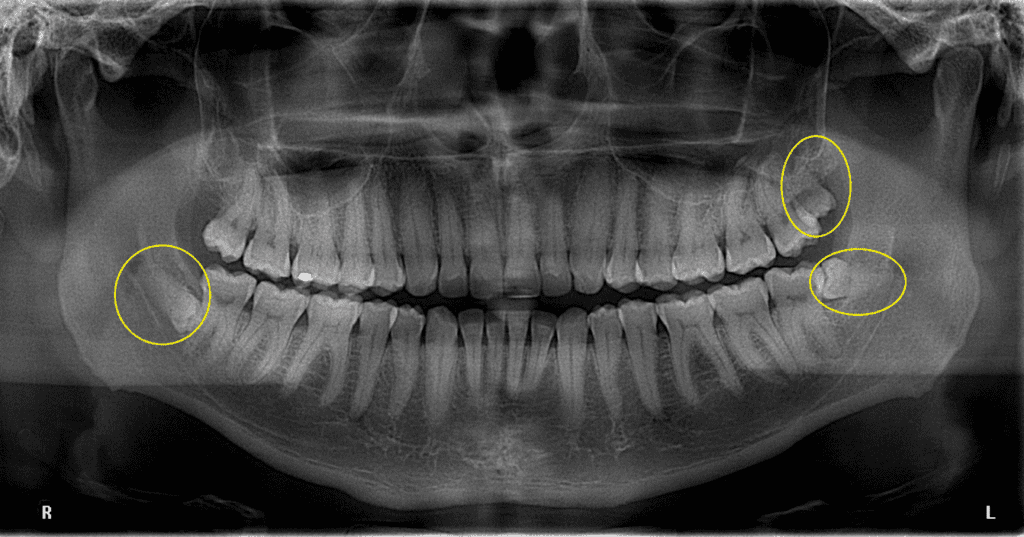

La Hiperdoncia

Supernumerario - Reabsorción Radicular

En el caso de un diente supernumerario, es esencial conocer su ubicación precisa y su relación con otras estructuras dentales…